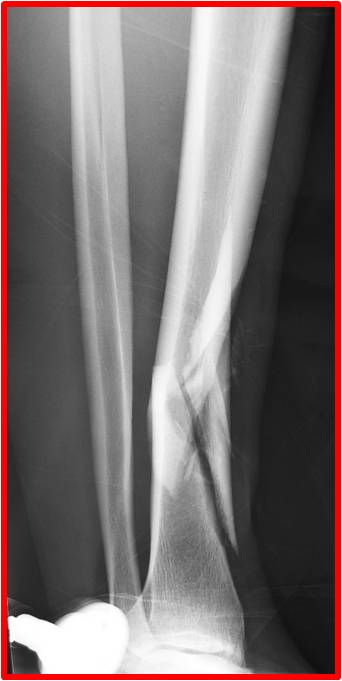

Fractures de la jambe